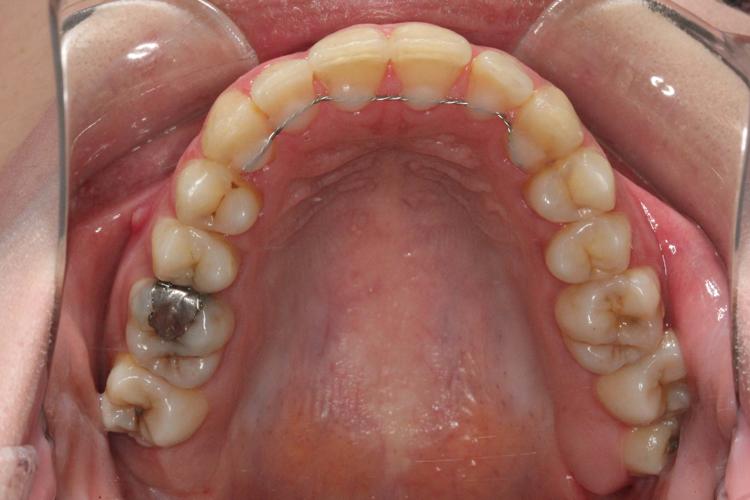

نتایج درخشان قبل و بعد از ارتودنسی در ستاره شرق

نتایج درمانهای ارتودنسی در کلینیک ستاره شرق